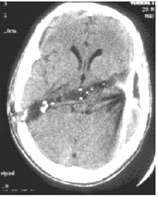

פצעי ירי בראש מאופיינים בנזק לעצמות הגולגולת ולמוח. בפצעי ירי אפשר למצוא: שברים בגולגולת, המטומה אפידורלית, המטומה סובדורלית, שטפי דם תוך-מוחיים, קרע של כלי דם גדולים והרס של רקמת המוח לאורך מסלול הקליע. האבחנה היא קלינית. ניתן לראות פצע כניסה ולעיתים פצע יציאה ושט"ד מקומי. ב-CT נראה את מסלול הקליע ונזקיו (תצלום 4.16). בצילום גולגולת ניתן לראות את הקליע או רסיסים בגולגולת ובמוח (תצלום 5.16). קליעים מכלי ירי צבאיים, שהם בעלי מהירות גבוהה, יוצרים נזק ניכר לעצמות ולמוח, כאשר הנזק לאורך מסלול הקליע כולל גם נזק היקפי סביב המסלול עקב החום והוויברציה שיוצר הקליע. לעומת זאת, קליעים בעלי מהירות נמוכה גורמים בעיקר לשטפי דם ונזק גרמי. הפרוגנוזה של נפגעים אלו גרועה ורוב הנפגעים, במיוחד הנפגעים מקליעים עם מהירות גבוהה, נפטרים מהפציעה או נשארים עם נכות ניכרת.